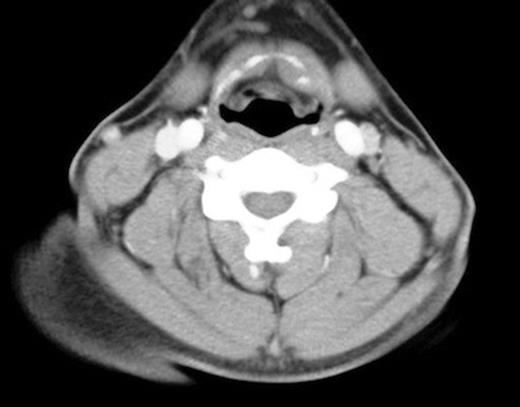

There was minor asymmetry of the valeculla and the left vocal cord (figure 2), but otherwise no significant airway compression. Management involved conservative treatment only with appropriate analgesia. On examination two weeks later, all his symptoms had settled. Repeat flexible nasal endoscopy showed only soft tissue swelling and minor asymmetry of the left valeculla.